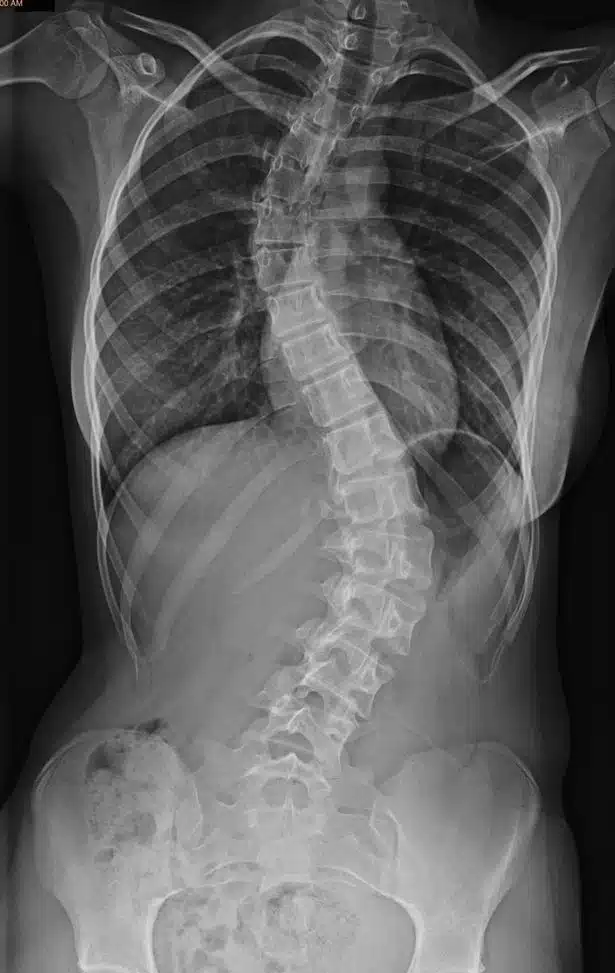

يمكن أن يحدث تضيق القناة لعدة أسباب. وأكثر سببين شيوعاً هما الشيخوخة والتهاب المفاصل. ويعود السبب في حدوث التهاب المفاصل إلى تلف الغضاريف، أو تطعيم العظام أو فرط نمو العظام. مع تقدم الإنسان بالعمر ، يتعرض جسم الإنسان لبعض العمليات التنكسية ، وقد تصبح الأنسجة في العمود الفقري أكثر سمكاً، وتنمو العظام بشكل أكبر من حجمها الطبيعي ، مما يشكل ضغطاً على الأعصاب. ويمكن أن تؤدي الشيخوخة أيضاً إلى حالات أخرى مثل الفُصَالٌ العَظْمِيّ (هشاشة العظام) والتهاب المفاصل الروماتويدي ، وكلاهما حالة التهابية يمكن أن تؤدي إلى تضيق القناة. يمكن أن يؤدي هشاشة العظام إلى حدوث تغييرات في القرص الفقري، وسماكة أربطة العمود الفقري ، وفرط نمو العظام، حيث تسبب هذه الحالات ضغطاً على الحبل الشوكي والأعصاب. ويمكن لأسباب أخرى بالإضافة إلى العمر والتهاب المفاصل ، أن تسبب تضيق القناة ومن هذه الأسباب ( العيوب الخلقية، انحناء العمود الفقري ، الجنف وأورام العظام ) بالإضافة إلى الأسباب المحتملة الأخرى مثل حدوث بعض الإصابات التي قد تسبب كسور أو التهاب في العمود الفقري أو بروز الأقراص الفقرية.

مُعظم الأشخاص المصابين بالتضيُّق الشوكي هم فوق سِنِّ 50. على الرغم من أن التغيُّرات الانتكاسية يمكن أن تسبب تضيُّق العمود الفقري لدى الشباب، إلَّا أَّن هناك أسباباً أخرى يجِب أخذُها في الاعتبار. وتشمل هذه الأسباب: الإصابة، تشوُّهات العمود الفقري الخِلقية مثل الجنف، والأمراض الوراثية التي تؤثر على نموِّ العظام والعضلات في جميع أنحاء الجسم. يمكن أن يُميز التصوير الفقاري هذه الأسباب.